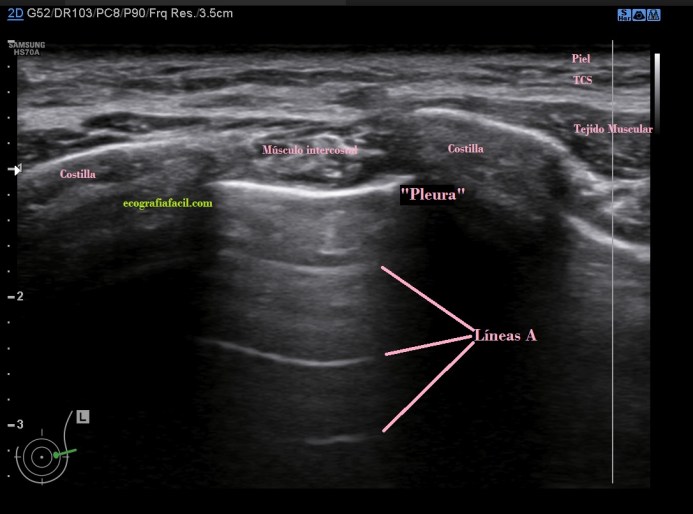

Si el pulmón está aireado y sano vamos a ver esta imagen:

Líneas A. En la imagen 1 puedes ver la normalidad de un pulmón bien aireado en esa región explorada. La anatomía radiológica, la imagen hiperecogénica que asociamos a la pleura y los artefactos en espejo de las tres líneas A paralelas a la línea que hemos denominado «Pleura» y que tan solo es la primera de las líneas especulares, es decir, artefacto de espejo que se produce entre la pared torácica y el aire del pulmón.

Artefacto de espejo que explica estas líneas y porqué se producen:

Es un error en la lectura de los ecos de retorno, me explico, cuando el haz llega a la estructura y vuelven al transductor lo hacen apropiadamente, pero hay otra parte del haz que llega a la siguiente capa hiperecogénica, que devuelve ecos que chocan contra la parte posterior de la primera interfase hiperecogénica, estos ecos tardan más en llegar al transductor y por tanto hace que parezca que está más profundo, es para explicarlo muy básicamente, una doble lectura en tiempos distintos. En ecografía el tiempo de lectura equivale a profundidad, por tanto la segunda lectura del objeto será incongruente y ocasiona esta falsa imagen en planos profundos.

En conclusión, la líneas A son de NORMALIDAD. Son hiperecogénicas, lineales, paralelas horizontalmente y equidistantes.